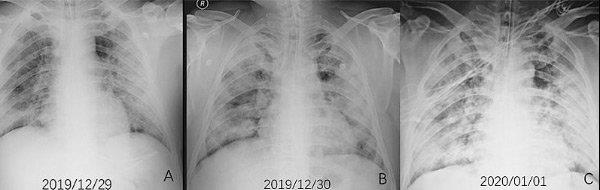

Koronavirüs belirti ve şiddetinin her hastada farklılık gösterdiğine dikkat çeken uzmanlar, hastalık sürecinin ağır geçirilmesinin nedenini, görevi vücutta virüsün çoğalmasını durdurmak olan Tip 1 İnterferon proteninin bulunmaması olarak gösteriyor.

Bazı kişiler Kovid19 için yaş ya da kronik hastalıklar açısından riskli grupta olmamasına rağmen bu hastalığı ağır geçirirken, bazı bireyler bu süreci belirtisiz ya da çok hafif atlatıyor. Kandan bakılan genetik bir testle bu konuda şimdiye kadar bilimsel olarak gösterilmiş tüm gen ve varyasyonların incelenmesi sağlanarak, hastalığı kimlerin ağır kimlerin hafif şekilde geçireceği belirlenebiliyor. Bu sayede kişi bir uzmana danışıp, Kovid19 konusunda alması gereken sosyal izolasyon, bireye özel tedaviler, bağışıklık güçlendirici uygulamalar gibi gerekli yaşam tarzı değişikliklerini hayatında yapabiliyor.

SİNYAL AĞI ÇOK ÖNEMLİ

Prof. Dr. Özen, "Bireylerin genetik yatkınlığı ve geçmişi, bu hastalığın seyri konusunda önemli ipuçları veriyor. Kovid19'u çok ağır geçiren, yoğun bakım tedavisi görmek durumunda kalan hastaların bir bölümünde doğuştan gelen genetik mutasyonlara rastlandığı ortaya konuldu. Bu hastalarda vücudu virüslerden koruyan ve 10'dan fazla proteinden oluşan Tip 1 İnterferon bulunmadığı belirtildi.

Hastalarda koronavirüsün ağır geçirilmesinin nedeni de Tip 1 İnterferon sinyal ağının bozulmasından kaynaklanıyor. Kovid 19 Genetik Yatkınlık Testi ile bunu tespit edebiliyoruz" dedi.